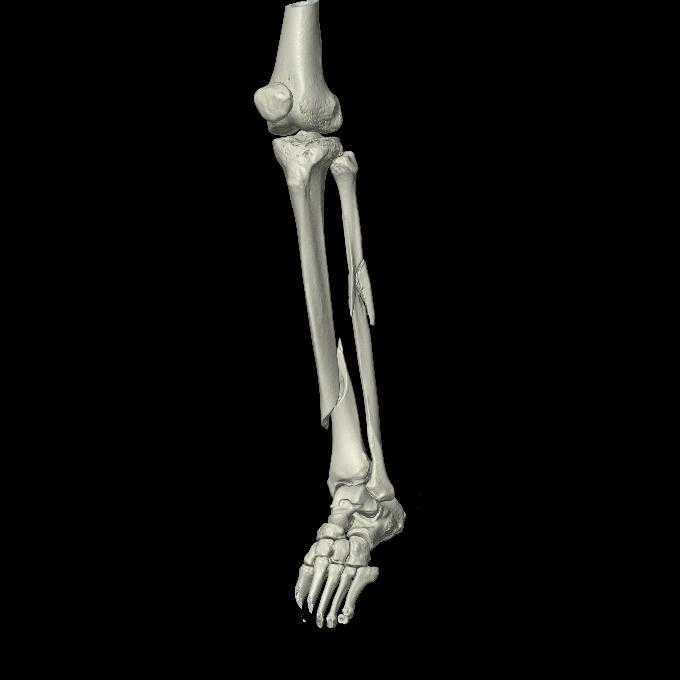

102803 1/12(キウスなし) 1/27 左下腿 4R 30歳女性 左脛骨軸内釘